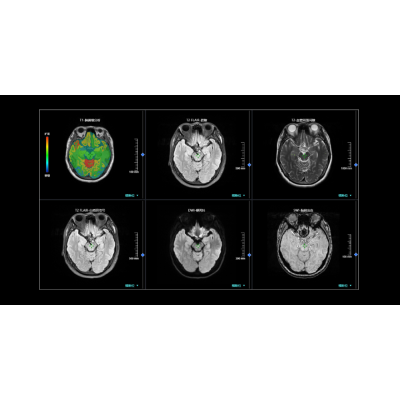

MR脑小血管病智能分析系统可辅助医生进行多序列同步对比阅片,实现整体工作流优化、节省阅片时间。该系统可全方位自动定量评估脑小血管病六大影像征象:近期皮质下小梗死、假定血管源性的腔隙灶、假定血管源性的白质高信号、扩大的血管周围间隙、脑微出血、脑萎缩。此外,基于检出结果可提供CSVD总负荷评分、一键生成脑小血管病影像评估报告,为脑小血管病的慢病防治与管理场景提供完善全面的综合解决方案。

联影智能MR脑小血管病智能分析系统能够辅助医生精准诊断脑小血管病,提高早期病变的检出率,帮助患者实现早发现、早治疗;通过提供全维信息,为医生制定更精准的治疗计划提供支持,且由于脑小血管病是长期隐匿进展的过程,AI所提供的随访功能可纳入患者全时间线的检查进行分析,实现脑小血管病患者的慢病全程管理。